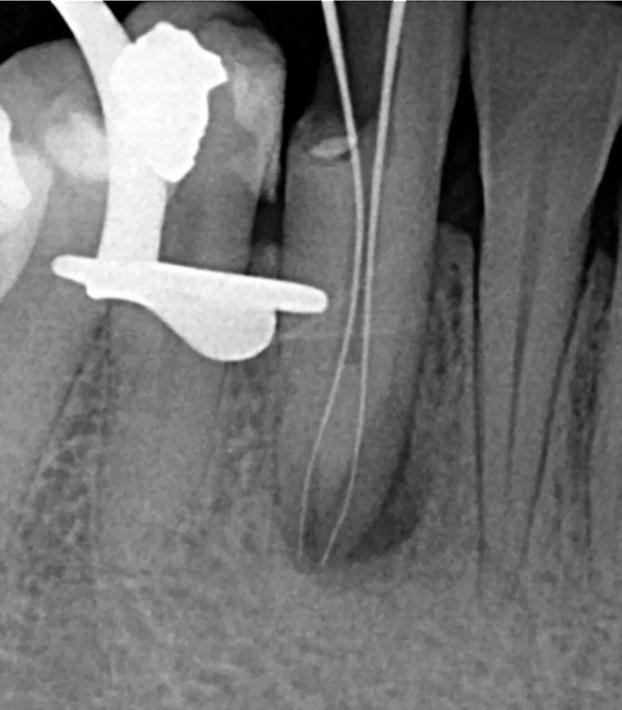

Infiltration of the local anesthesia (Lidocaine HCl 2% with epinephrine 1:100,000) was administered and the rubber dam was placed. Access to the cavity was achieved using a round diamond bur. The conventional lingual access opening was modified by including more of the incisal surface to gain sufficient access to the canals . The two orifices were located one buccally and one lingually. Coronal flaring was carried out using the Sx file of the ProTaper system (Dentsply-Maillefer, Ballaigues, Switzerland). The two canals were carefully instrumented with a size 15 K-file . The working length of the canals was established with the use of apex locator (Root ZX: J Morita Co, Kyoto, Japan) and verified radiographically (Fig.4).

4